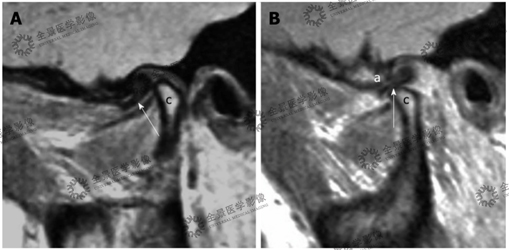

病史:一名56岁女性患有颞颌关节弹响。

结论:可复性关节盘前移:A.闭口位示下颌髁突前方(c)的前移关节盘(白箭头);B.张口位示关节盘(白箭头)复位至下颌髁突(c)与颞骨(a)之间。